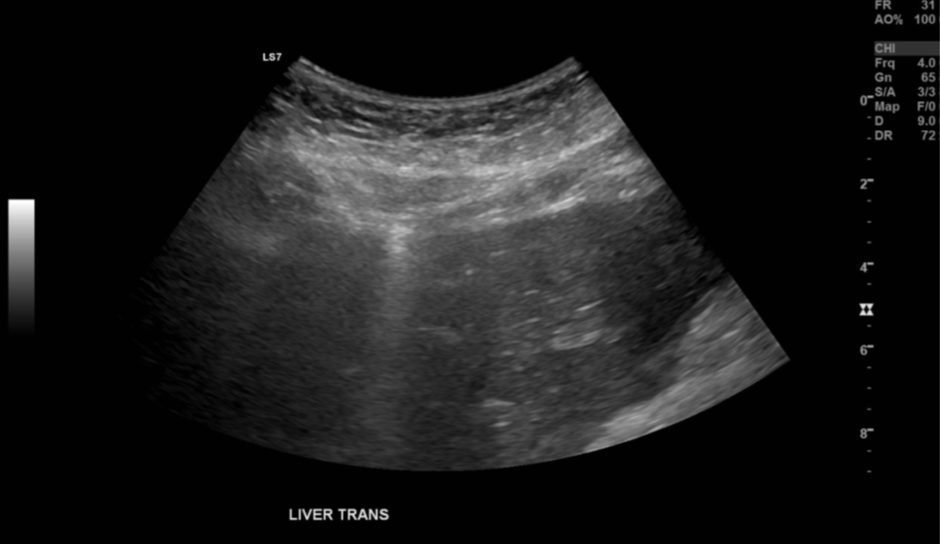

No abnormality was detected in the spleen, liver, biliary tree, pancreas, kidneys or aorta. There was no ascites. However, images 1 and 2 demonstrate the patient’s region of pain.

Figure 1. Image of the left lobe of liver in transverse. |

Small pockets of gas with ring down artifact are seen along the peritoneal line.

Upon scanning, the patient was acutely tender in the epigastrium. When lying in the left posterior oblique position, ringdown artifact starting just superficial to the left lobe of the liver was noted. This artifact was subtle but reproducible when scanning in different positions and corresponded to the patient’s main region of pain.